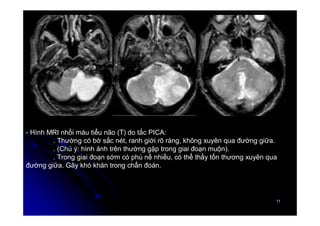

- Hình MRI nhồi máu tiểu não (T) do tắc PICA:

. Thường có bờ sắc nét, ranh giới rõ ràng, không xuyên qua đường giữa.

. (Chú ý: hình ảnh trên thường gặp trong giai đoạn muộn).

. Trong giai đoạn sớm có phù nề nhiều, có thể thấy tổn thương xuyên qua

đường giữa. Gây khó khăn trong chẩn đoán.